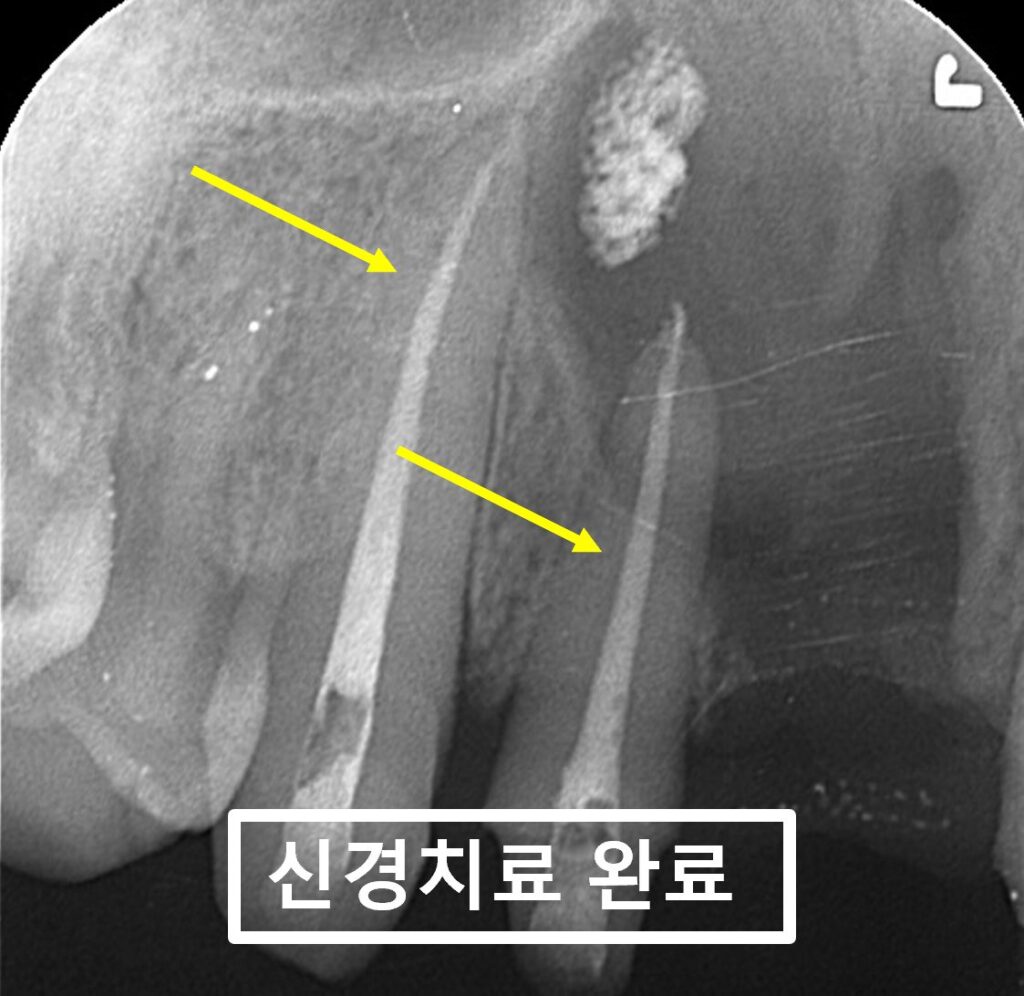

24.05.07(1회신경치료) – 43y 김OO님

거대 치근단낭종의 제거 수술을 위해

2개치아의 신경치료를 먼저 시행하고

촬영한 x-ray 사진입니다.